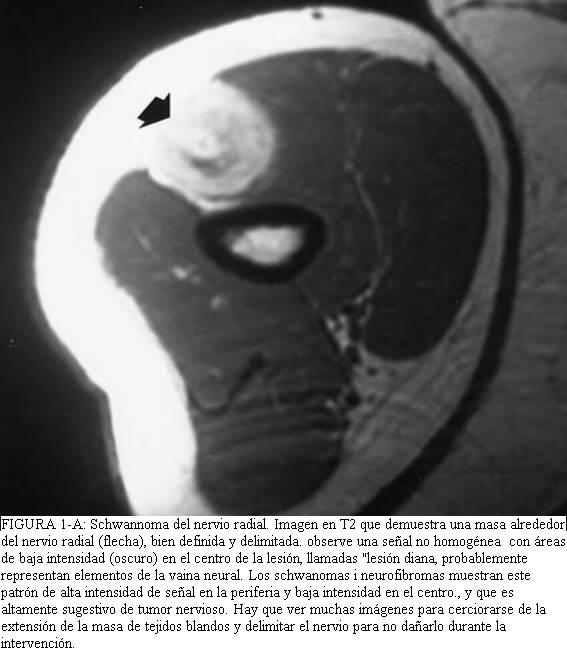

El examen físico normalmente muestra una masa sin dolor que es móvil en todos los planos excepto la dirección longitudinal del nervio. La resonancia magnética muestras una masa excéntrica que se nervio origina de un periférico. La resección local puede lograrse por la definición del plano entre el tumor y el nervio periférico. Una vez esto el plano se desarrolla, el tumor puede disecarse libre del nervio.